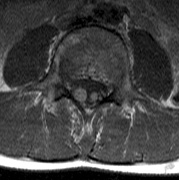

first used in 1936.166 The first major clinical criteria for the syndrome were proposed in 1964.167 The main manifestations of von Hippel-Linau syndrome are: histologically similar hemangiomas of the retina and CNS, renal cysts, renal cell carcinomas, pancreatic cysts, pheochromocytomas, and endolymphatic sac tumors.13 EPIDEMIOLOGY The prevalence of VHL syndrome is about 1 in 35,000 to 40,000.168 It is autosomal dominant with greater than 95% penetrance by age 60 years.169 Its expression, even within the same family, may be quite variable, especially for renal disease and pheochromocytoma.170,171 SYSTEMIC FEATURES Cutaneous Findings Cutaneous findings are not part of the diagnostic criteria for VHL syndrome. Neurologic Findings CNS hemangiomas are the most common tumor of VHL, affecting 60% to 80%, with a predilection for the cerebellum and spinal chord. An enlarging cystic component is a frequent finding in symptomatic tumors. Patients typically present in their early 30s; headaches or neck pain in affected individuals should not be ignored.172,173 On microscopy, CNS hemangiomas resemble retinal capillary hemangiomas. Their malignant potential is low.174 The treatment is surgical (Fig. 17, A and B).13 Endolymphatic sac cystadenomas are a sensitive marker of VHL. Patients may present with hearing loss, tinnitus, disequilibrium or facial nerve palsy.175,176 Visceral Findings KIDNEY. Renal cysts are often asymptomatic and do not require treatment. However, complex cysts may carry a risk for malignant transformation. Renal carcinoma affects about a third of patients. Patients typically present in their late 30s. These tumors may be completely asymptomatic, underscoring the necessity for ultrasound screening.13,177 ADRENALS. Pheochromocytomas are benign neural crest tumors of the adrenal medulla (chromaffin cell derived) and probably affect 10% to 20% of patients. Mean age at diagnosis is at about 30 years of age. Pheochromocytomas may be multiple and bilateral. They are catecholamine-secreting tumors that classically produce severe hypertension and anxiety attacks, but they may also be asymptomaic.178 The National Cancer Institute classification of VHL syndrome is in part based on the absence (type I) or presence (type II) of pheochromocytoma (Table 5).171